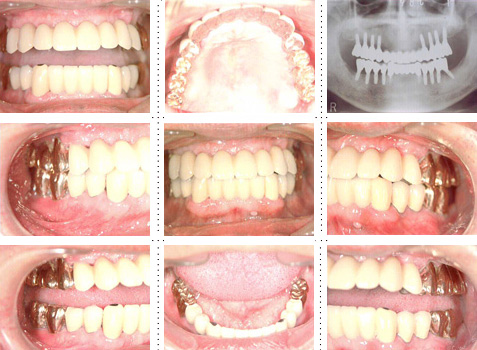

症例4

57才 女性

知人の歯科医からのご紹介。良く噛めない為、元気が出ない。介護の仕事を続けるためにも、歯を治療して自分がもっと元気になりたい。最初は部分的に治療する予定だったのですが、歯のない部分はインプラントを埋入し、最終的には上下顎全ての歯を治療し、しっかりものが噛めるようになりました。